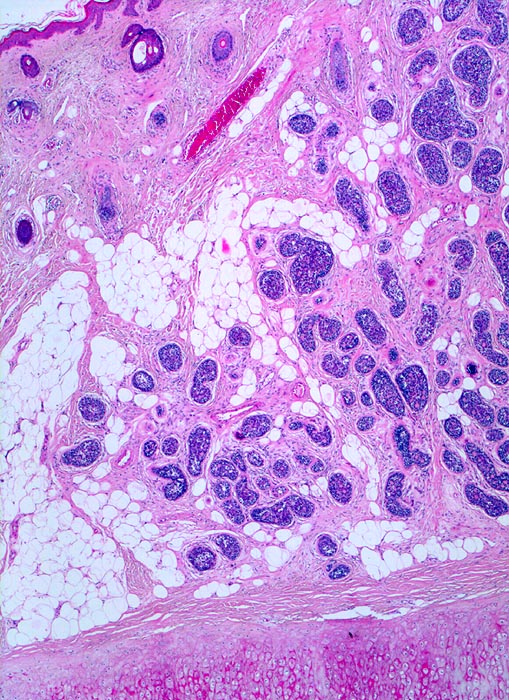

p/ Adenoidzystisches Karzinom der Haut

Adenoidzystisches Karzinom der Haut

Das zytologische Bild ist täuschend bland. Die Tumorzellen sind klein und monomorph, die Kern-Zytoplasmarelation ist hoch. Die Kerne sind dunkel, rund bis oval oder angulär und enthalten bisweilen einen kleinen Nukleolus. Typisch sind azelluläre Matrixkerne, um die die Tumorzellen angeordnet sind.